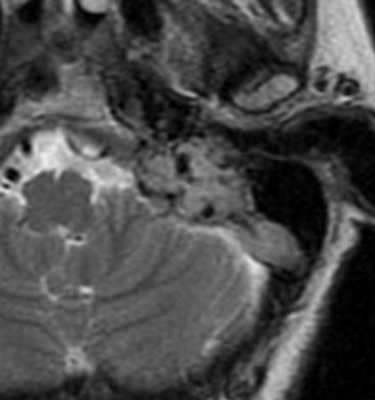

МРТ головного мозга. Т2-взвешенная аксиальная МРТ. Опухоль югулярного гломуса слева (фрагмент).

При МРТ в СПб наибольшую сложность мы видим в дифференциальной диагностике такого редкого варианта строения яремной вены с опухолью. Опасность состоит в ошибочной биопсии с фатальным кровотечением. Надо сказать, что яремные вены в норме часто несимметричны, типично расширение с одной стороны и расположение может быть высоким, вплоть до внутреннего слухового прохода. Кроме аномального расположения луковицы яремной вены, пульсирующий шум во внутреннем ухе может быть связан с опухолью югулярного гломуса, одного из вариантов хемодектом. При опухоли югулярного гломуса опухоль располагается большей частью в яремном отверстии, но также распространяется на клетки височной кости и Гальвезиев канал. Таким образом, происходит разрушение нижней стенки височной кости с переходом в среднее ухо.

Год назад пациент самостоятельно отметил появление новообразования в наружном слуховом проходе при выполнении туалета уха, снова обратился к врачу. Только на этом этапе было выполнено дообследование в объеме КТ и МРТ височных костей. Согласно результатам лучевой диагностики, при КТ височных костей (от 15.12.2014 г.) обнаружены признаки новообразования левой височной кости с остеолитической деструкцией (рис. 1); по результатам МРТ сосудов головного мозга от 10.04.2015 г. выявлены МР-признаки патологического участка сосудистого новообразования в области пирамиды левой височной кости, вероятнее всего - гломусная опухоль луковицы левой яремной вены.

Было выполнено повторное МРТ головного мозга с контрастированием от 4.09.2015 г.: МР-картина, вероятнее всего, соответствует гломусной опухоли слева. МР-данных за очаговое поражение вещества головного мозга и мозжечка не получено.